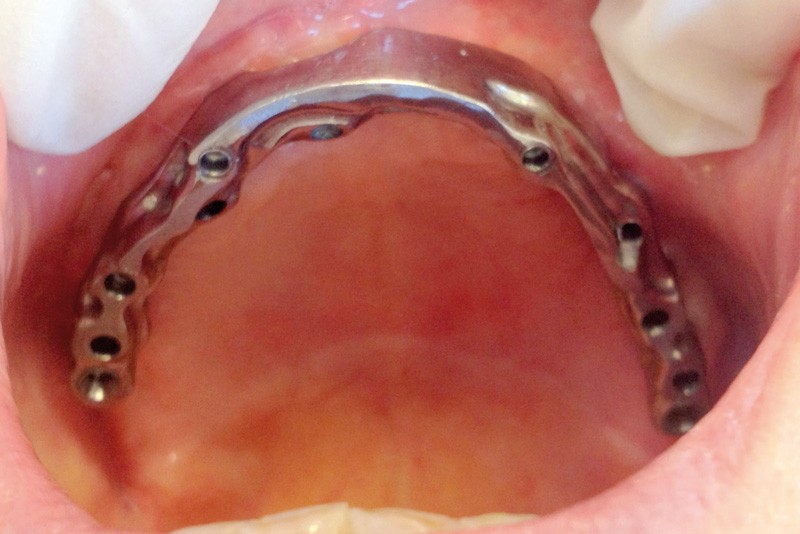

Un Dentascan® permet d’évaluer le volume osseux disponible pour une réhabilitation implanto-portée en complément de la radio panoramique de première intention. Cet examen confirme l’atrophie osseuse maxillaire (fig. 1 et 2).

En conséquence, une solution implantaire passe nécessairement par une reconstruction osseuse préalable. Une sur-élévation bilatérale des planchers sinusiens est réalisée avec un abord latéral. Les comblements des zones sous-sinusiennes sont effectués au moyen d’os allogénique (Maxgraft®) mélangé à un coagulum veineux prélevé en début d’intervention puis recouvert d’une membrane de collagène Bio-gide® et de PRF’s. La prothèse totale est évidée et rebasée périodiquement avec une résine souple.